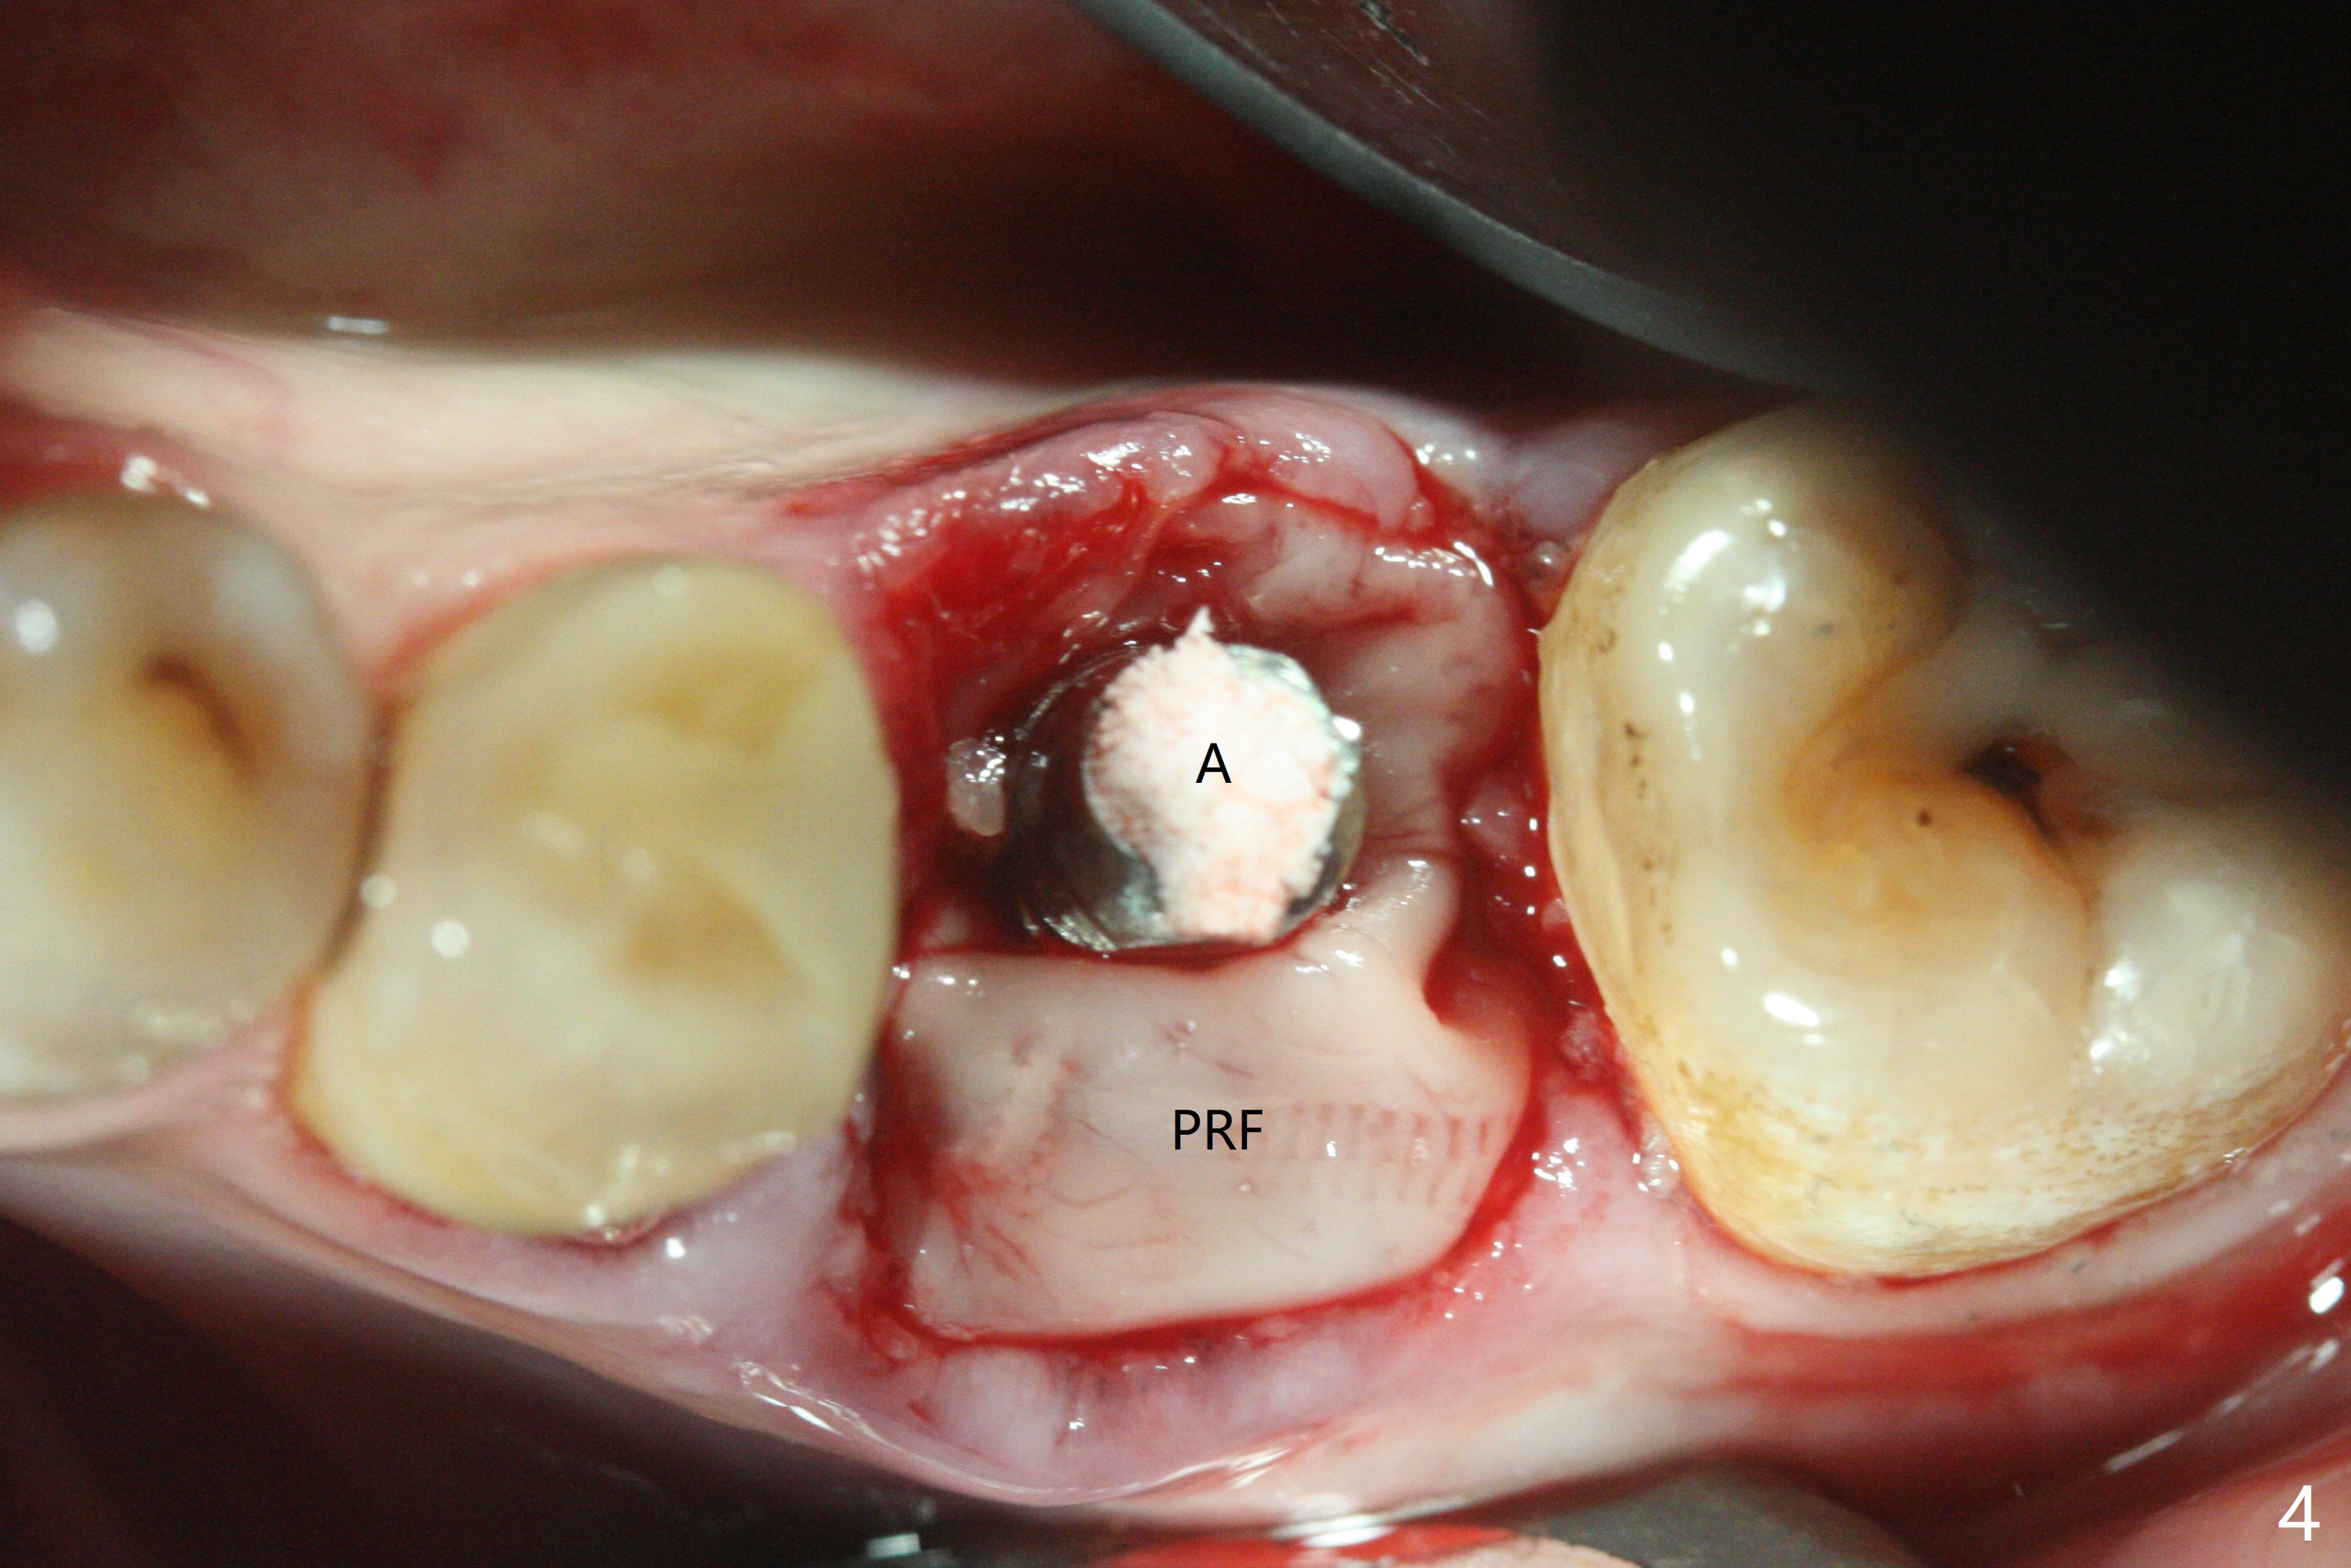

54岁男左下6根管治疗不成功,远中舌侧根弯曲,拔除时牙齿牙根多次断裂,骨质也硬,即使使用2.2毫米钻头也很吃力,钻至11.5毫米深,拍摄根尖片,显示钻洞没有明显偏移(图一),临床观察一致。当钻头直径增大,浅部钻洞,震动大,深部时,震动慢慢减少。为了植入5x11毫米植体,钻头必须4.5毫米,植体还必须反复倒旋转,才能减少扭力至40Ncm。由于没有骨质阻挡,基台放置尚顺利(图二)。拔牙时舌侧远中骨壁破坏,植入粘性骨粉重点放入 (图三:*),表面覆盖一张PRF膜(图四),最后制作临时牙冠。术后1.5月调整临时牙冠,牙槽窝愈合正常(图五)。